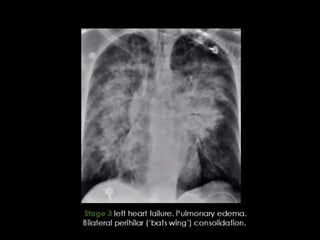

-Pulmonary oedema is a broad descriptive term and is usually

defined as an abnormal accumulation of fluid in the extra-vascular

compartments of the lung 1

.

-HRCT findings in cardiogenic pulmonary edema

Bilateral septal thickening and ground-glass opacity.

Perihilar and gravitational distribution predominatly in the

dependent lung.

Cardiomegaly and pleural fluid.